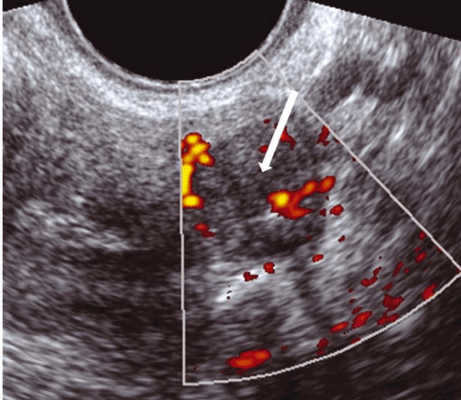

Опухоли с метастазами в яичниках были обозначены, как рак яичников. Если опухоль была ограничена только поверхностью яичника, с не захваченной стромой яичника. Она была классифицирована как овариальная с карциноматозом. Опухоли, которые прикреплены к стенке таза и кровоснабжаются внешней, внутренней или общей подвздошной артерией; или опухоли, расположенные четко под париетальной брюшиной, были классифицированы как ретроперитонеальные. Гетерогенные, бессосудистые участки смешанной эхогенности с размытыми границами, прилегающие к васкуляризованной ткани, были классифицированы, как участки вероятного некроза (рис.1).

Рис.1. Некроз: гетерогенный бессосудистый участок с неровными краями (стрелка) в окружении ткани, которая кровоснабжается.

Как правило, неходжкинская лимфома располагалась в малом тазу экстраперитонеально, имела плотную структуру и гетерогенное содержимое в виде гиперэхогенных и гипоэхогенных участков (рис 4). Допплерография показала гиперваскуляризацию опухоли.

Рис.4. Метастазы лимфомы: хорошо определена гетерогенная опухоль с множественными гиперэхогенными включениями (1) и с гипоэхогенными участками (2).